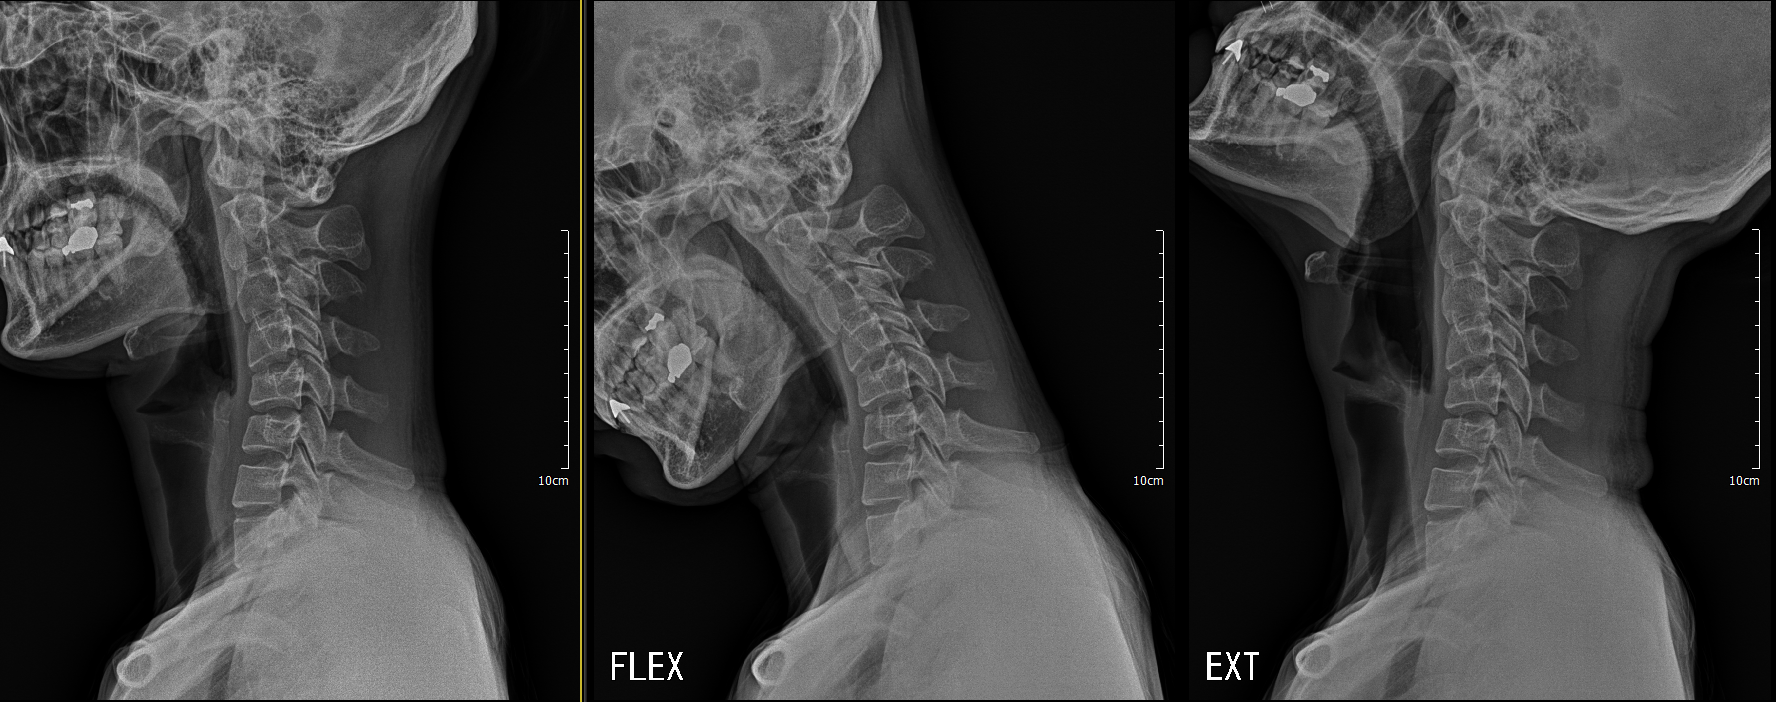

목이 정상적이라면, C자 형태의 곡선으로 이룹니다. 하지만 요즘은 스마트폰과 컴퓨터 사용량이 증가함에 따라 고개를 앞으로 쭉 숙이거나 오랫동안 숙이는 잘못된 자세를 유지하거나 외부 충격으로 인해 목 근육이 경직되면, 일자형 또는 역 C자 형태 곡선을 이루게 됩니다. 이에 따라 젊은 연령층에서도 목이 딱딱해지고 통증을 느끼고 어깨까지 통증이 느껴지는 거북목 증후군을 앓는 분들이 늘어나고 있습니다. 또한 해당 질환은 현대인들의 만성질환이라고 불릴 정도로 많은 분이 많이 겪는 질환 중 하나인데, 이에 따라 증상을 발견하더라도 방치하는 경우가 많아 여러 통증과 목 디스크 등과 같은 2차 질환을 유발하게 됩니다.

거북목 x ray 추가